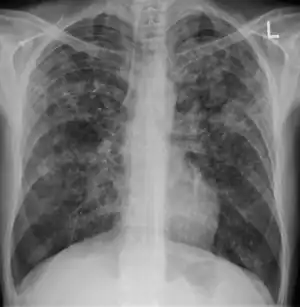

Chest X-ray of a person with advanced tuberculosis: Infection in both lungs is marked by white arrow-heads, and the formation of a cavity is marked by black arrows.